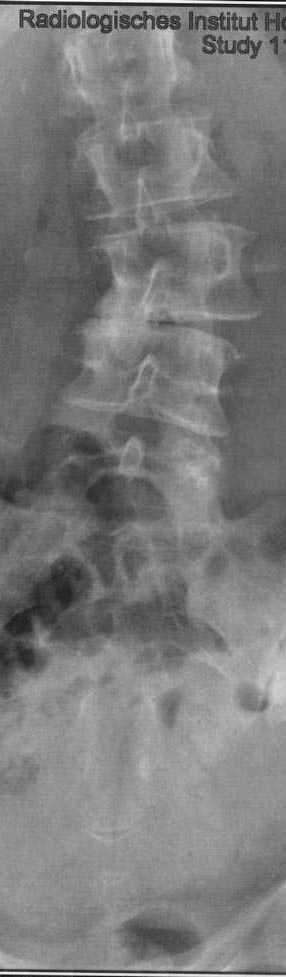

So, dann wurde eine ganze Aufnahme der Wirbelsäule gemacht und der Skoliosewinkel bestimmt. Im Befund steht:

"Linkskonvexe Torsionsskoliose der LWS mit kompensatorischer rechtskonvexer Schwingung der unteren BWS. Die LWS zeigt einen Skoliosewinkel von 14 Grad und die BWS von 12 Grad."

Ok, den Winkel der LWS sehe ich recht deutlich, den der BWS sehe ich nicht :D .

Kann es sein, dass bei so unterschiedlichen sichtbaren Krümmungswinkeln nur ein Unterschied der Gradzahl von 2 Grad vorliegt, oder ist hier irgend etwas schief gelaufen.

Deine Röntgenaufnahmen sind leider zweigeteilt, so dass sie zur Beurteilung einer Skoliose nur bedingt geeignet sind (z.B. Messungenauigkeit viel höher und es kann nicht beurteilt werden, ob du im Lot stehst). Wurde denn im Stehen oder im Liegen geröntgt? Wenn du Taubheitsgefühle angibst und du langanhaltende Schmerzen hast, dann sollte auch mal ein MRT gemacht werden.

Also ich bin kein Arzt, aber die Krümmung in der LWS sieht nach wesentlich mehr als 14° aus, tippe eher auf´s doppelte. Auch sieht es so aus, als ob du schon degenerative Veränderungen hast (der gekippte Wirbel sieht aus, als ob dort die Bandscheibe einseitig verschlissen ist), steht davon denn was im Befund? Es würde auch eher zu deinen angegebenen Beschwerden (insb. den Taubheitsgefühlen) passen, als eine reine Mini-Skoliose. Könnte auch sein, dass du keine "normale" Skoliose hast, sondern die erst aufgrund dieser degenerativen Veränderungen entstanden ist. Wie gesagt, ich bin kein Arzt und kann dir daher nur raten, mal einen Spezialisten aufzusuchen.

die oberen Bilder sind im Stehen gemacht.

Die unten eingefügte Ganzaufnahme auch.

Auch bei dieser Aufnahme habe ich den Eindruck, dass man einen Unterschied von 2 Grad eigentlich gar nicht sehen dürfte, oder?

Rein aus dem Bauch heraus geschätzt, beträgt Deine LWS Krümmung gut 30°.

Was die Schmerzen angeht, so könnten die - wie von Minimine schon erwäht - auf den Akgekippten Lendenwirbel zurück gehen. Evtl. hast Du auch an den anderen LWS Wirbelkörpern und Bandscheiben degenerative Prozesse.

Ich bin ganz Deiner Meinung, 2° kann man nicht unterscheiden und ganz sicher ist die LWS-Krümmung deutlich höher als die BWS-Krümmung.

Die klinisch optische Einschätzung lässt sich nicht unmittelbar auf denCobb-Winkel übertragen. Hierbei ist zu beachten, dass im vorliegenden Falle die Verkrümmung der LWS sich im Bereich weniger Wirbelbilder ausbildet. Sie Skoliose der BWS erstreckt sich über mehr als doppelt so viele Segmente. Ihr folgt ausgleichend eine Gegenschwingung der HWS.

Bei der Vermessungsaufnahme der ganzen Wirbelsäule gewinnt man die Gesamtübersicht auf Kosten der Messgenauigkeit.

Nach elektronischer Bilddemontage und Vergrößerung, würde man die Neutralwirbel eventuell different zu der Gesamtaufnahme bestimmen. Dies hätte etwas andere Messwerte (HWS !0 Grad, BWS 14 Grad, LWS 18 Grad) zur Folge. Dabei ist zu beachten, dass die sekundäre Manipulation der Aufnahmen ebenfalls fehlerbehaftet ist."